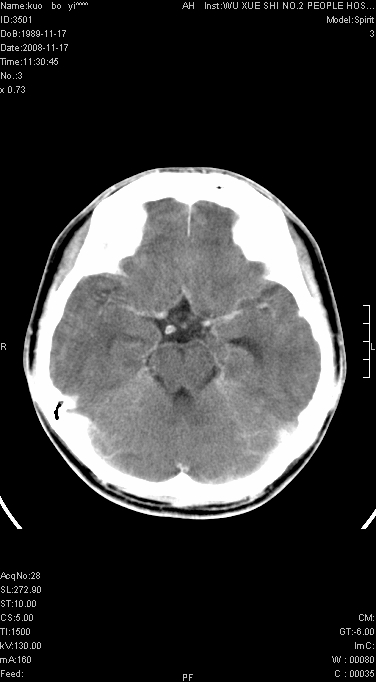

增强已传.年龄19岁.请会诊

增强后水肿中心高密度灶有明显强化,强化不均匀,呈雪花状或絮状,且强化明显,若为肿瘤,应该出现形态较规则的瘤体影,强也有例外如胶质瘤就可以形态不规则.但胶质瘤明显强化者多为恶性间变性,与病史及相关表现太不相符.因此本例多考虑为炎症引起.

左顶叶较大范围水肿区,内见明显强化的片状 棉絮状组织,但占位效应不明显。多考虑:脑炎!

还是考虑原发脑胶质瘤,梗塞缺血水肿的低密度要同时累及皮、髓质并要符合动脉供血的区域分界特点,本例强化后见瘤体结节及向周围浸润生长的瘤血管都强化了,水肿广泛呈指状,占位效应使同侧脑皮质受压变薄、脑沟消失但因实质性的瘤体尚小所以中线无明显移位。不知各位同意这样分析吗?(转移瘤多为多处病灶)

首先考虑脑胶质瘤。有明显的左顶叶脑白质水肿,病变轻度占位效应,花环样强化,脑炎——影像不支持!

左顶叶大范围水肿,内见明显强化的片状 棉絮状组织,但占位效应不明显。考虑脑炎可能性大。

在北京天坛医院治疗考虑寄生虫感.明显好转